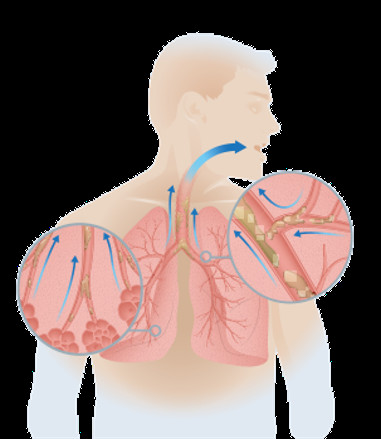

Portable Healthcare Vest Airway Clearance System Cough Assist For Child& Adult

Portable Healthcare Vest Airway Clearance System Devices 220V Images |